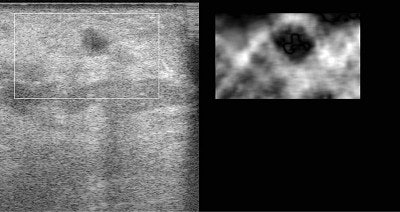

| The above image has some of the features typical of breast cancer: the tumor is hypoechoic (dark compared to its surroundings), and has an irregular boundary. The palpation image (an image of relative mechanical strain) of this lesion shows that the lesion is stiffer than its surroundings (dark compared to its background), and appears larger in the palpation image than in the B-mode image. |